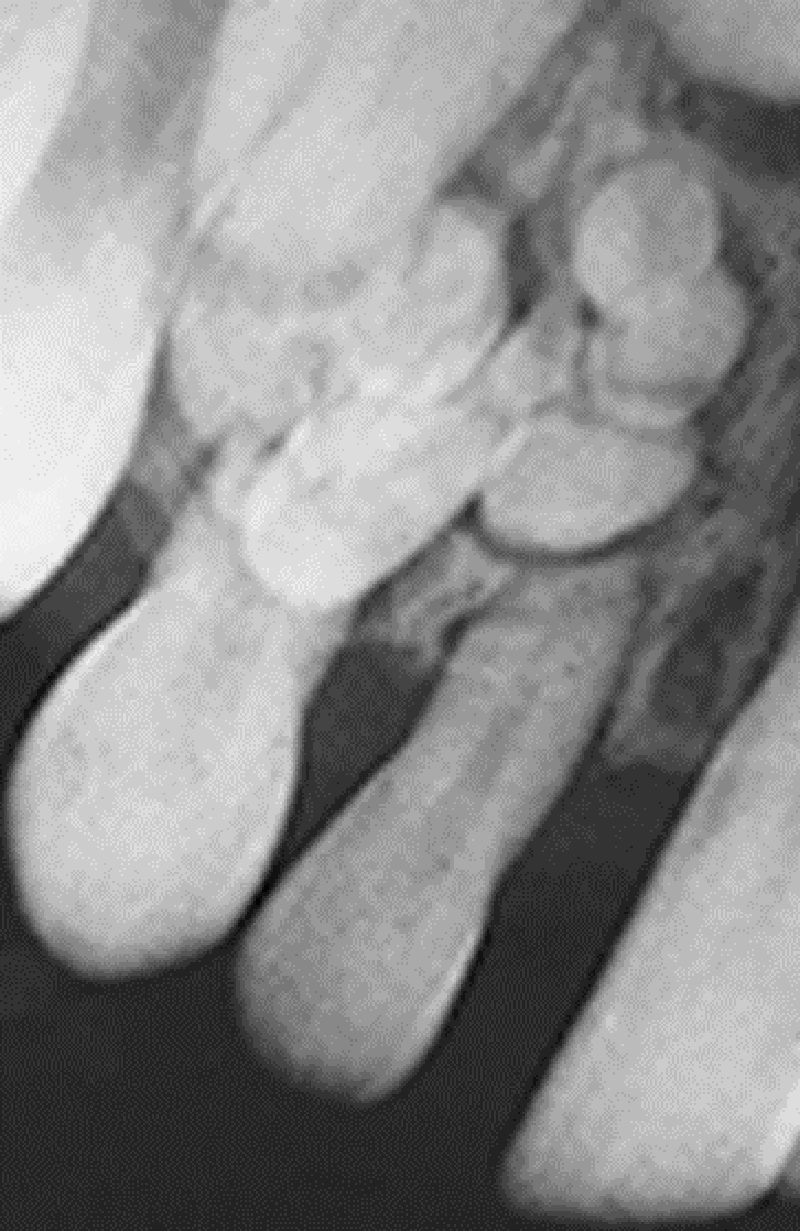

{"name":"Oral Path ID Chapter 6-9", "url":"https://www.quiz-maker.com/QPREVIEW","txt":"This condition is linked with Keratinosis of the palms of the hands & the soles of the feet. Individuals with this condition are likely to experience tooth mobility and premature tooth loss., This Term is used to describe The Appearance of type III (hypomaturation) Amelogenesis Imperfecta, Radiographs of a person with this condition appear to have a multilocular or “soap bubble” appearance","img":"https://www.quiz-maker.com/3012/CDN/92-4508546/final-pic-1.png?sz=1200"}